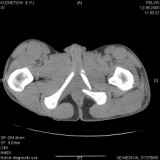

Уважаемые коллеги! Хотелось бы услышать совет по тактике лечения представлленого больного.Поступил после лечения в одном изотделений области. Травма 2,5 месяца назад. После выведенияиз шока был произведен остеосинтез перелома бедра, предплечья, до перевода к нам проводилосьвытяжение по оси шейки бедра за стержень, введенный в большой вертел. На сегодня деформацияригидна, клинически мобильности не определяется. Заранее признателен. P.S. Данный вид травм не включен в перечень "высокотехнологичных операций", направить длялечения по квотам Минздрава очень сложно.

Это обзорные и косые снимки

С уважением,

Leonid

Тяжелый случай... Поздняя реконструкция такого перелома технически сложное дело, вероятность осложнений,неуд.результатов выше(на PubMed article Johnson, Mast, Matta, Letournell results of acetabular reconstruction 20-120 days after injury).

Принимая во внимание обширность реконструкции, вероятность осложнений( остеоартроз, аваскулярный некроз), которые в любом случае должны будут решаться артропластикой сустава, пожалуй, я бы не стал оперировать сейчас: складывать мозаику многооскольчатого перелома, мобилизуя фактически сросшиеяся воедино фрагменты - дело травматичное с сомнительным результатом.